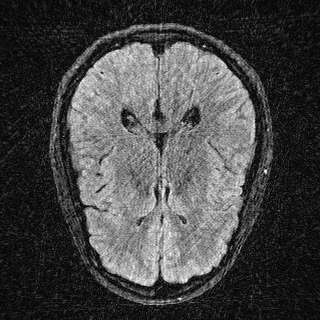

This article presents a novel undersampled magnetic resonance imaging (MRI) technique that leverages the concept of Neural Radiance Field (NeRF). With radial undersampling, the corresponding imaging problem can be reformulated into an image modeling task from sparse-view rendered data; therefore, a high dimensional MR image is obtainable from undersampled $k$-space data by taking advantage of implicit neural representation. A multi-layer perceptron, which is designed to output an image intensity from a spatial coordinate, learns the MR physics-driven rendering relation between given measurement data and desired image. Effective undersampling strategies for high-quality neural representation are investigated. The proposed method serves two benefits: (i) The learning is based fully on single undersampled $k$-space data, not a bunch of measured data and target image sets. It can be used potentially for diagnostic MR imaging, such as fetal MRI, where data acquisition is relatively rare or limited against diversity of clinical images while undersampled reconstruction is highly demanded. (ii) A reconstructed MR image is a scan-specific representation highly adaptive to the given $k$-space measurement. Numerous experiments validate the feasibility and capability of the proposed approach.